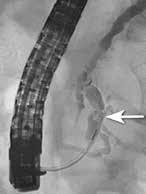

Obstruksjon av pankreas hovedgang Årsaken til smerter ved kronisk pankreatitt er multifaktoriell men kan hos mange, spesielt i tidlig fase av tilstanden (før pasienten blir opiatavhengig), forklares helt eller delvis av økt trykk i pankreas hovedgang på grunn av obstruksjon av fløde av pankreassaft. Obstruksjonen er oftest forårsaket av strikturer og konkrementer i caput eller collum og gir dilatasjon av hovedgangen. Obstruksjon lenger oppstrøms i corpus og cauda har sjeldnere klinisk relevans. Den vanlige og minst invasive tilnærmingen er å plassere en plaststent forbi obstruksjonen i hovedgangen som trykkavlastning for å se om dette bedrer smertene. Dersom effekt kan man fortsette stentbehandling og evt. gå videre med andre invasive tiltak. ESGEs retningslinje fra 2018 foreslår endoskopisk terapi og/ eller ekstrakorporal sjokkbølge-litotripsi (ESWL) som førstevalg for smertefull, kronisk pankreatitt med obstruerende konkrement og dilatasjon av hovedgang i caput eller corpus. Imidlertid viste ESCAPE-studien fra 2020 og en senere langtids oppfølgingsstudie at tidlig (opiatavhengighet < 6 mnd.) kirurgi var bedre enn endoskopisk behandling i å gi smertelindring både på kort og lang sikt. Pasienter operert tidlig hadde også mindre reintervensjoner enn pasientene med endoskopisk behandling. Nyere retningslinjer fra ASGE (2024) anbefaler derfor tidlig MDT vurdering med tanke på kirurgi. Det er imidlertid mange faktorer som påvirker valg av terapi, inklusiv pasientens ønske, komorbiditet og alder, og all invasiv (endoskopi/kirurgi) behandling har dårligere effekt jo lenger ut i sykdomsforløpet man har kommet. Tidspunkt for intervensjon kan være like viktig som valg av prosedyre, og beslutning om valg av terapi krever ekspertise og nøye risikovurdering i hvert enkelt tilfelle. All endoskopisk intervensjon på pankreas er beheftet med komplikasjoner som post-ERCP pankreatitt, blødninger, perforasjon og infeksjon. Pasienter med kronisk pankreatitt har dessuten økt risiko for adenocarcinom i pankreas som er en viktig differensialdiagnose ved dilatasjon av pankreas hovedgang eller forverring av symptomer hos pasienter med kronisk pankreatitt.

Små konkrementer i pankreas hovedgang (< 5 mm) kan ofte fjernes endoskopisk ved at strikturer dilateres og konkrementet hentes

ut med konvensjonelle metoder (Fig 4). Større konkrementer er mer krevende og kan behandles med ESWL eller pankreatikoskopi og fragmentering av konkrement(ene) med sjokkbølgelitotripsi eller laser. Selv om man tilsynelatende klarer å fjerne alle konkrementer fra hovedgangen er tilbakefallsfrekvensen høy og pasientene risikerer langvarig stentbehandling (vanligvis en eller flere plaststenter) og gjentatte endoskopiske prosedyrer.

Standard behandling av benigne strikturer har vært ERCP med gjentatte dilatasjoner og innleggelse av multiple plaststenter i gallegang over en periode på ett år (Fig 5). De senere år har bruk av selvekspanderende metallstent i 6-12 mnd. blitt mer vanlig dersom forholdene teknisk ligger til rette for dette. Det er imidlertid risiko for residiv av striktur på grunn av progresjon av grunntilstanden så gjentatt endoskopisk behandling kan bli nødvendig.